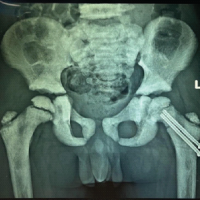

Distal neurovascular status was intact. Plain radiographs demonstrated dorsal dislocation of the left index MCP joint consistent with a chronic Kaplan’s dislocation (Fig. 2a and b). A schematic representation of the anatomical configuration responsible for Kaplan’s lesion is illustrated in Fig. 2c.

Figure 2: (a and b) Anteroposterior and lateral view radiographs of the left hand showing a dislocated second metacarpophalangeal (MCP) joint. Radiograph showing comparison between the unaffected right side and the affected left side in both anteroposterior and oblique views to confirm dislocation of the left second MCP joint. (c) Schematic illustration demonstrating the anatomical configuration in Kaplan’s lesion showing the flexor tendons, lumbrical muscle, natatory ligament, superficial transverse ligament, and digital neurovascular bundle forming a constricting noose around the metacarpal head.